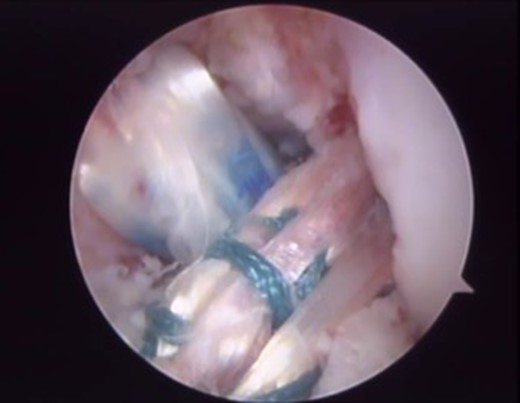

The patient underwent arthroscopic ACL reconstruction using ipsilateral flexor tendons as graft, PCL reconstruction using contralateral flexor tendons as graft and partial meniscectomy (Figs 3–5).

Arthroscopy surgery view during cruciate ligaments reconstruction. Note in (A) and (B) the ligaments absence. The lateral meniscus has not its bone tibial insertion of the posterior horn (*), which continued with the anterior meniscus femoral ligament (Humphry), which was hypertrophied (**). LFC, lateral femoral condyle.

Final arthroscopic surgery image of the ACL and PCL reconstruction with the grafts tense and well positioned.